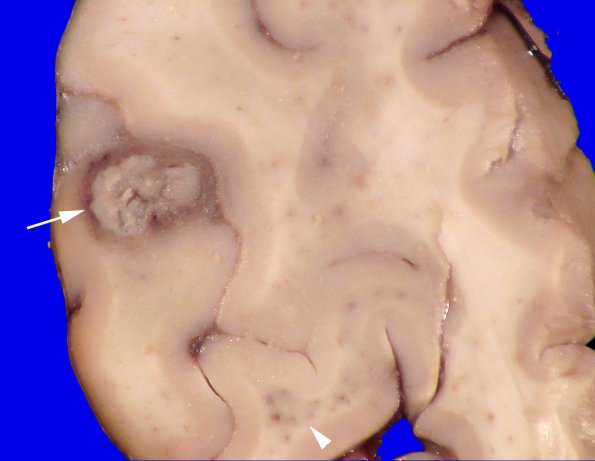

Origination from the gray/white junction, purulent contents and a hyperemic rim (arrow) characterizes this abscess. A second lesion (arrowhead) is also visible.